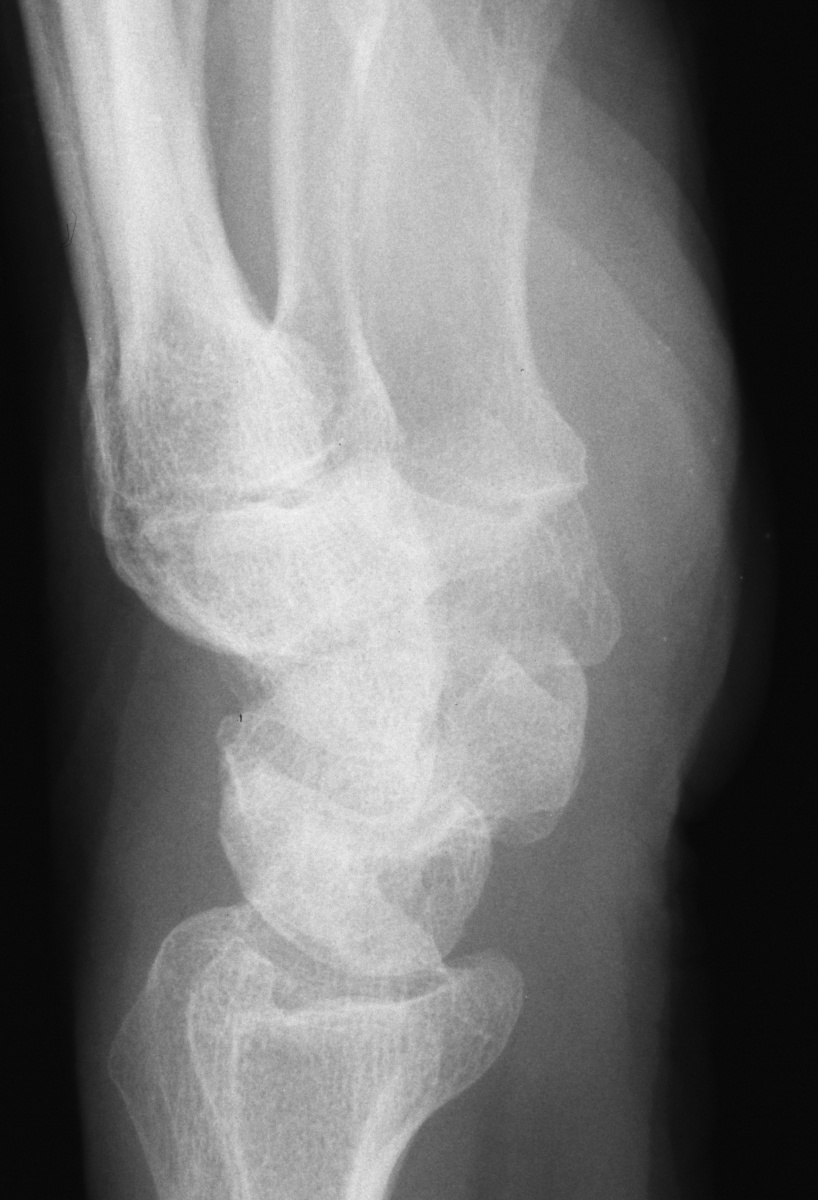

Clinical Example: Lunate Cyst

This imaging series was obtained for evaluation of a one month history of painful pronosupination in an active 85 year old man whose daily exercises include pushups.

lunate cyst